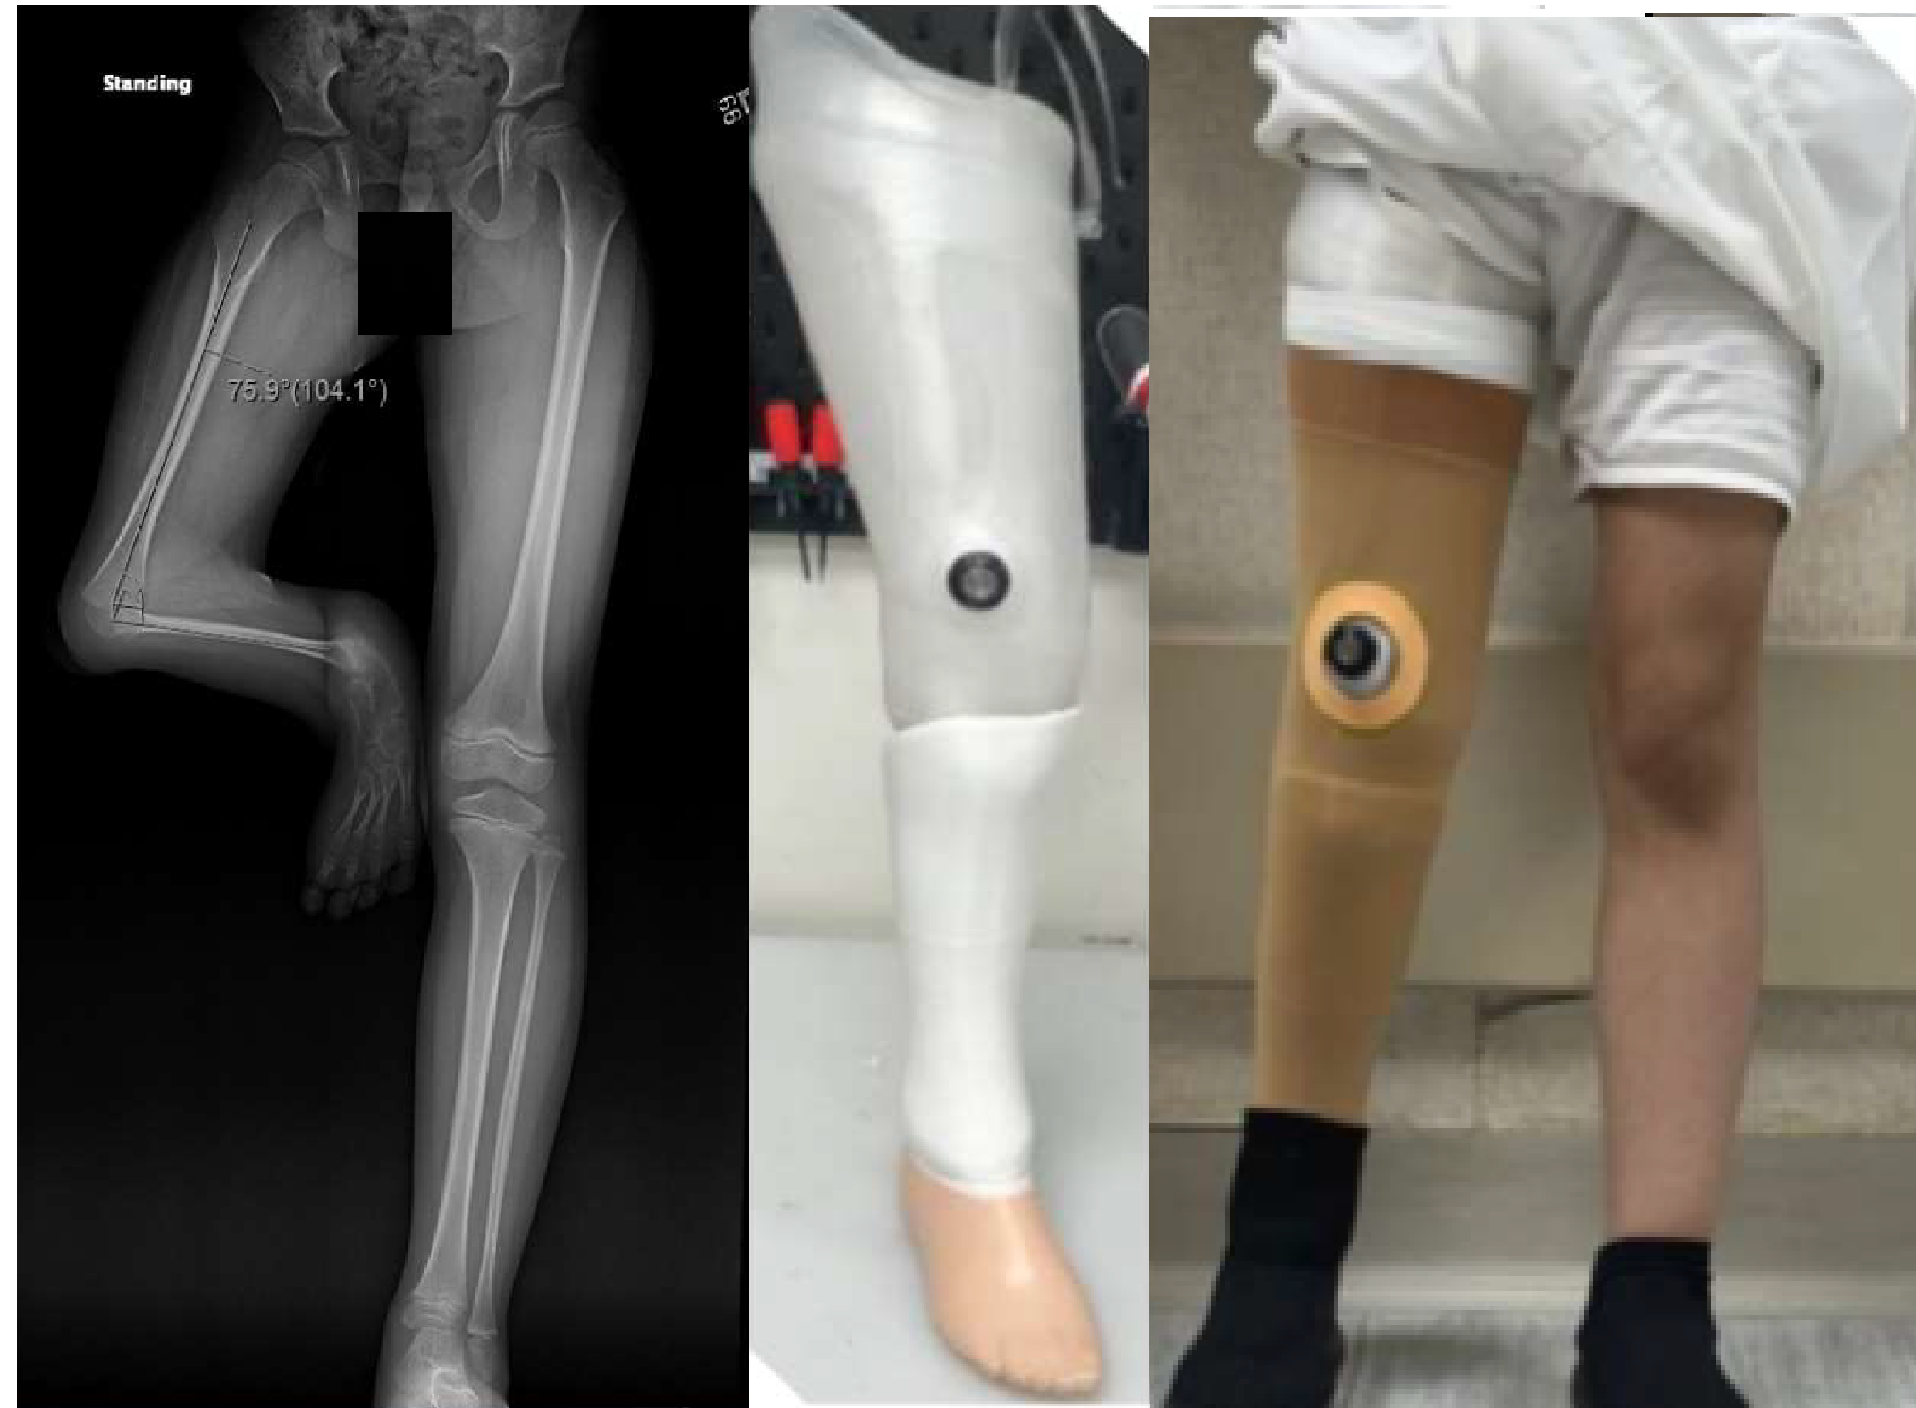

When Master “Fh” was born on March 23, 2015, in Riyadh, Saudi Arabia, his family’s joy was quickly overshadowed by the challenges they were about to face. Fh came into the world with a rare condition—complete tibial deficiency, Jones type 1A. His right leg had no tibia, and his foot was severely deformed, with his knee fixed in a position that made it impossible for him to walk like other children.

For years, Fh found a way to move using his right knee, despite its severe flexion of over 100 degrees, but the limitations were stark. His ankle and foot were completely nonfunctional, and X-rays revealed the absence of the tibia, along with a severely deformed foot. Reconstructive surgery was not an option.

‘’Two months after the surgery, Fh was ready for his first prosthesis. A through-knee prosthesis was custom-made for him, and the day he stood on it for the first time was unforgettable. For the first time in his life, he stood tall, balancing on both legs. He took his first independent steps, a moment that brought tears of joy to his parents and a sense of accomplishment to our team.” Mr. Imran recalled those moments.

A year later, Fh’s story took another extraordinary turn. At KFSH&RC, we introduced advanced 3D printing technology to prosthetics, and Fh became the first patient in Saudi Arabia to be fitted with a 3D-printed knee disarticulation prosthesis.

This new prosthesis was lighter, more comfortable, and highly functional. With it, Fh could do things that once seemed unimaginable—jumping, running, and playing like any other child his age. Watching him move with such freedom and joy was a testament to how far he had come.